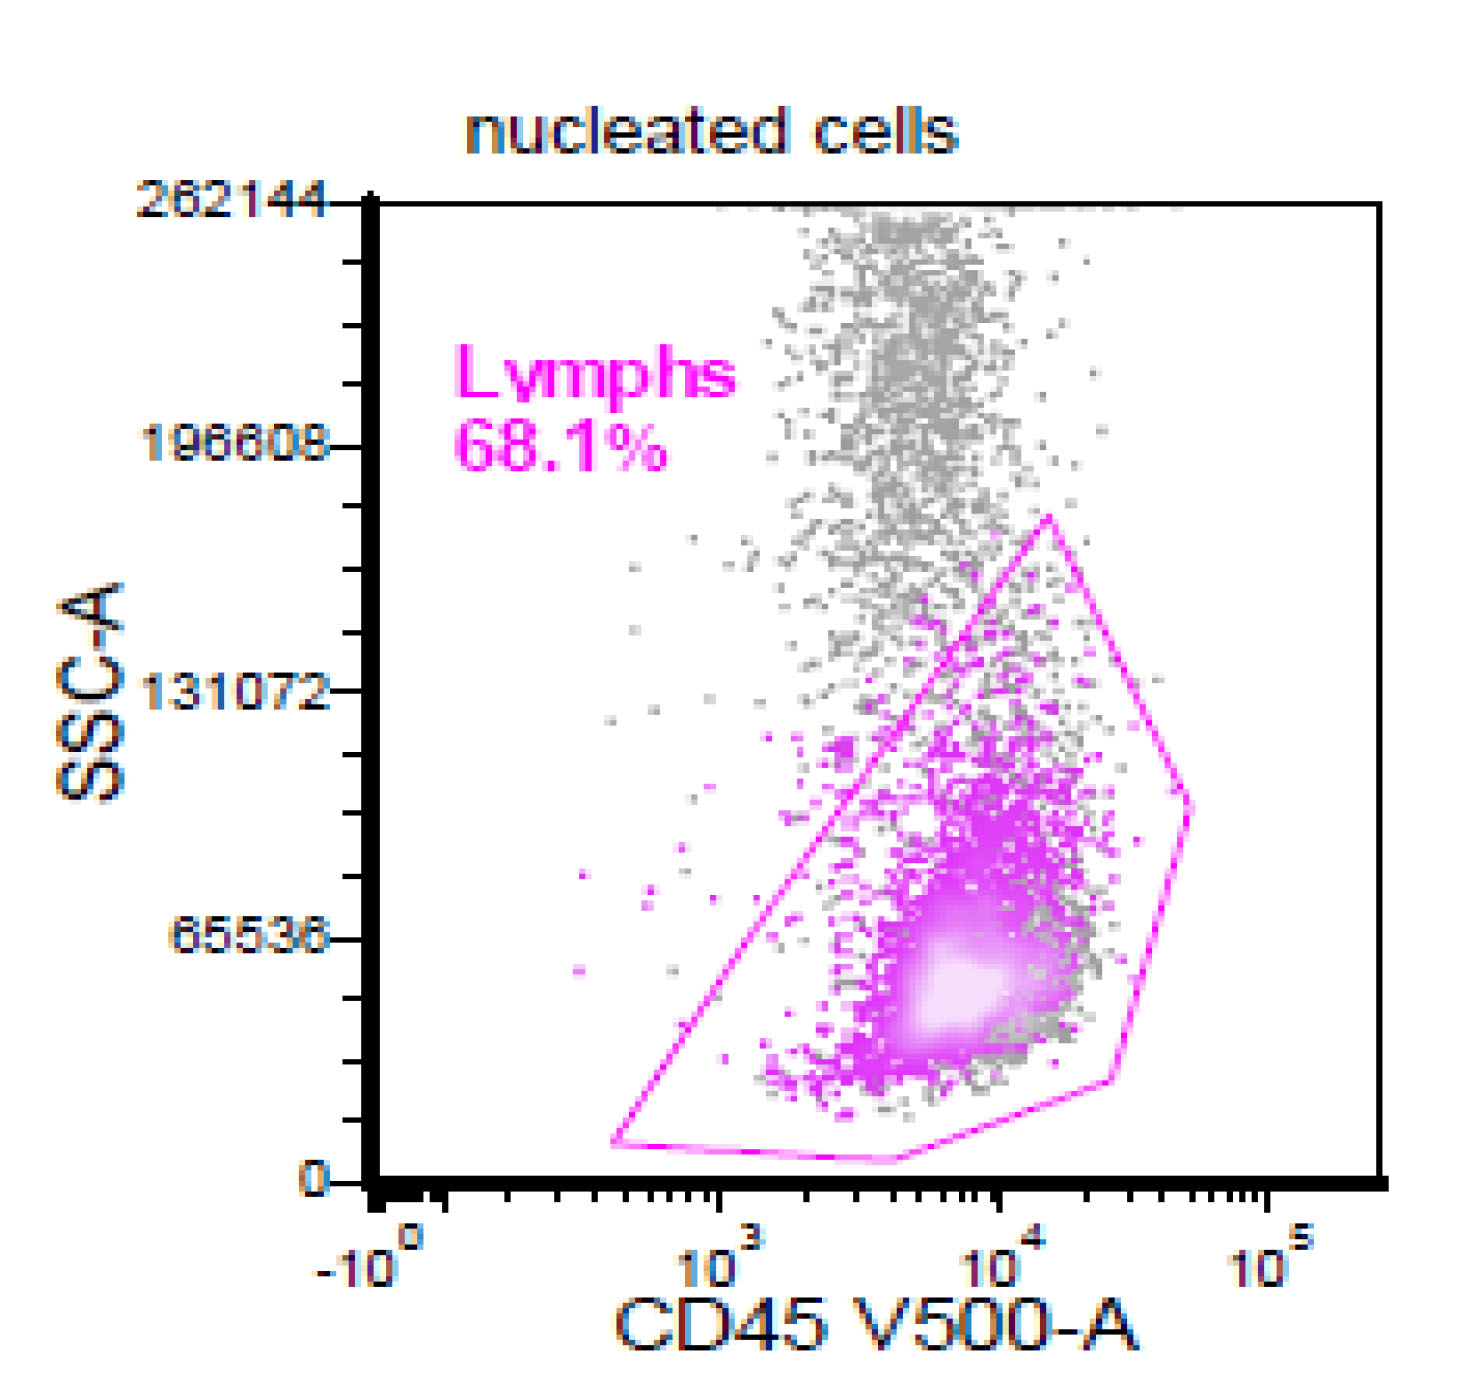

Flow cytometry description

- CD5+, CD19+, CD20+, CD22+, CD79b+, FMC7+

- Monotypic Ig (high level expression of surface light chains)

- CD11c variable, CD43 variable, CD200 variable

- CD3-, CD10-, CD23-

- Rare cases have atypical immunophenotype:

- CD5- or CD10+, CD200+ or CD23+ (dim ~10%)

Flow cytometry images

- This is the concurrent fine needle aspiration flow cytometry of the lymph node in a 70 year old man with lymphadenopathy. Cytology smears show intermediate to large lymphoid cells in a necrotic background. What is the most probable preliminary diagnosis before further work ups on the excised lymph node?

- Nodal marginal zone lymphoma

- Follicular lymphoma, grade 3A

- Mantle cell lymphoma

- Chronic lymphocytic lymphoma